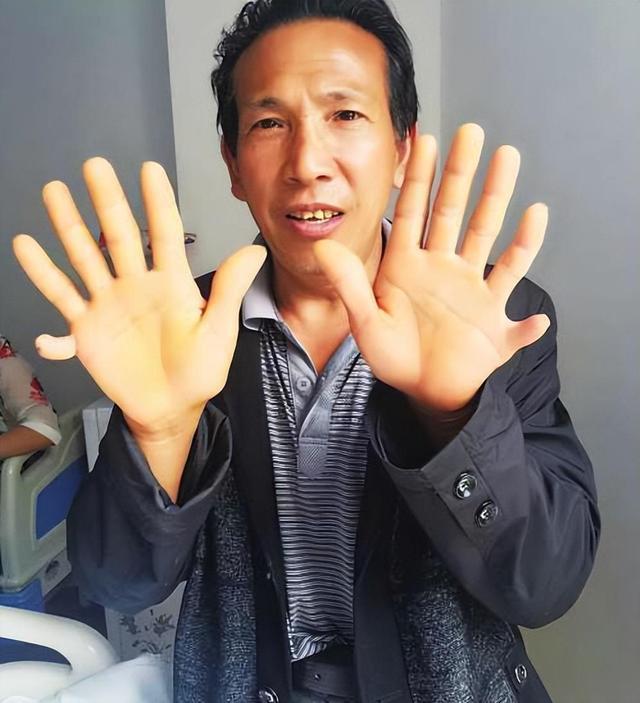

当这名男子出现在医院时,接诊医生在震惊的同时又羡慕不已,背地里夸他是“真男人”。医院的小护士们得知此事,纷纷前来围观。面对众人的疑问,男人的妻子微微一笑,骄傲地说:“他的身体素质很好!”

诊断结果出来后,在场的医生在震惊的同时,也对王开炼的情况羡慕不已。原因无他,因为他的的确确长了四个肾!

妻子终于放心下来,但让她没想到的是,丈夫住院恢复期间,医院的小护士们听得有人长了四个肾,纷纷前来围观。但大家若有所思地看着她时,她只好回应说:“我丈夫的身体素质的确很好。”

“我爷爷、爸爸有没有多出来的肾,我也不太清楚,但却存在多指的情况。”王开炼回答得很坦然。